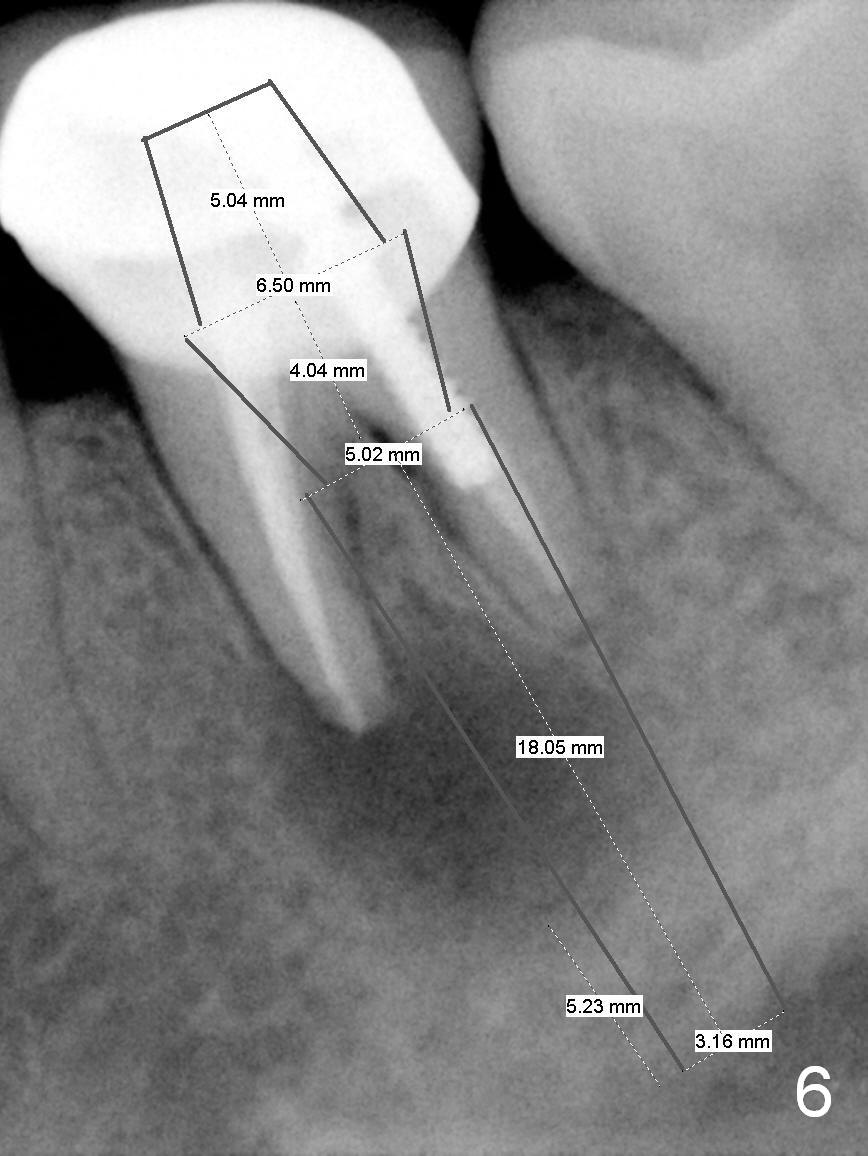

A 58-year-old lady has a long-standing periapical lesion with several episodes of acute infection (Fig.1-3, taken 10, 9 and 2 years ago, respectively). Explore the socket for size and wall integrity (Clindamycin). If the bony defect is not extensive, place a longest implant (18 mm bone-level, 20 mm tissue-level) with moderate diameter (5.5, 6 mm). Otherwise use a shorter, but wider tapered implant (7x12 mm (bone-level), 7 or 8x17 mm (tissue-level)). If the socket is extremely large, consider using 7 or 8 x20 mm cylindrical tissue-level implant. Use Bicon 2 mm pilot drill with extension to measure the socket depth and obtain 3-6 mm new bone or until 20 mm (gingival margin). Take PA. The 1st option is to use UF 3-4.7x18 mm drills at 50 RPM. Make sure that the depth is reached (septum crestal level) and check osteotomy wall integrity after each drill. Then place a 5 or 5.5x16 or 18 mm implant (Fig.6). The 2nd and 3rd options are shown in Fig.4 and 5. Due to severe infection and pain, a shorter implant is placed.